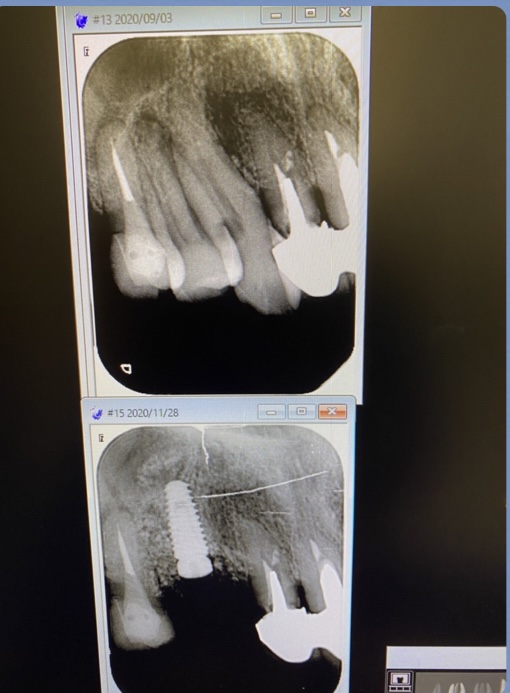

連続ソケットオペ

本日は理事長による午前/午後とインプラントオペが連続して行われました。

2症例共にソケットリフト法を併用するオペです。

(午前オペ/抜歯即時埋入)

患者さんにとって、抜歯と同時にインプラント埋入はオペが一度で済む利点がありますね